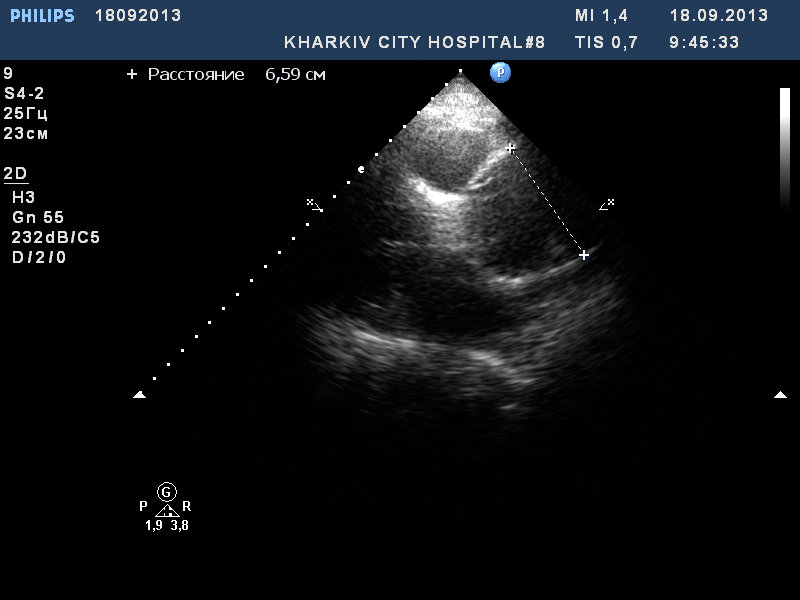

расслаивающая аневризма корня и восходящего отдела аорты

пациентка 67 лет. нелеченный гипертоник. Стала резко задыхаться. Интенсивных болей не отмечала. Попала в оит.

Собственно картина расслаивающей аневризмы корня и восходящего отдела аорты